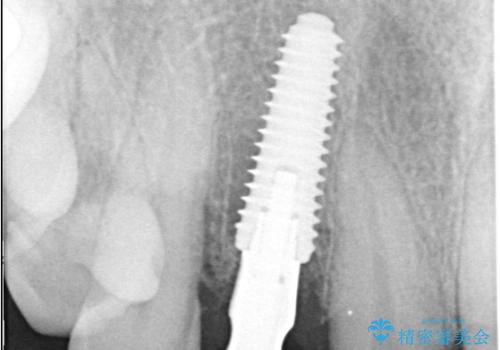

インプラント治療は、低侵襲で短期間に行える「抜歯即時インプラント治療」を選択しました。

この方法は、抜歯したその日にインプラントを埋入し、手術が1回で済むのが大きな特徴です。

治療期間も短く、抜歯からわずか3か月でオールセラミッククラウンを装着することができます。

また、オペ当日には仮歯まで装着するため、見た目を気にせず普段通りの生活を送ることができます。